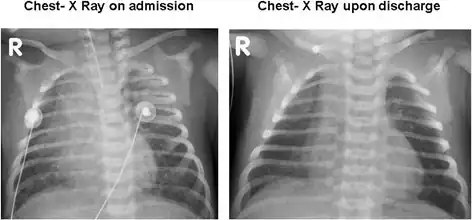

Bilateral patchy infiltrates due to pulmonary hemorrhage on admission and resolution upon discharge.